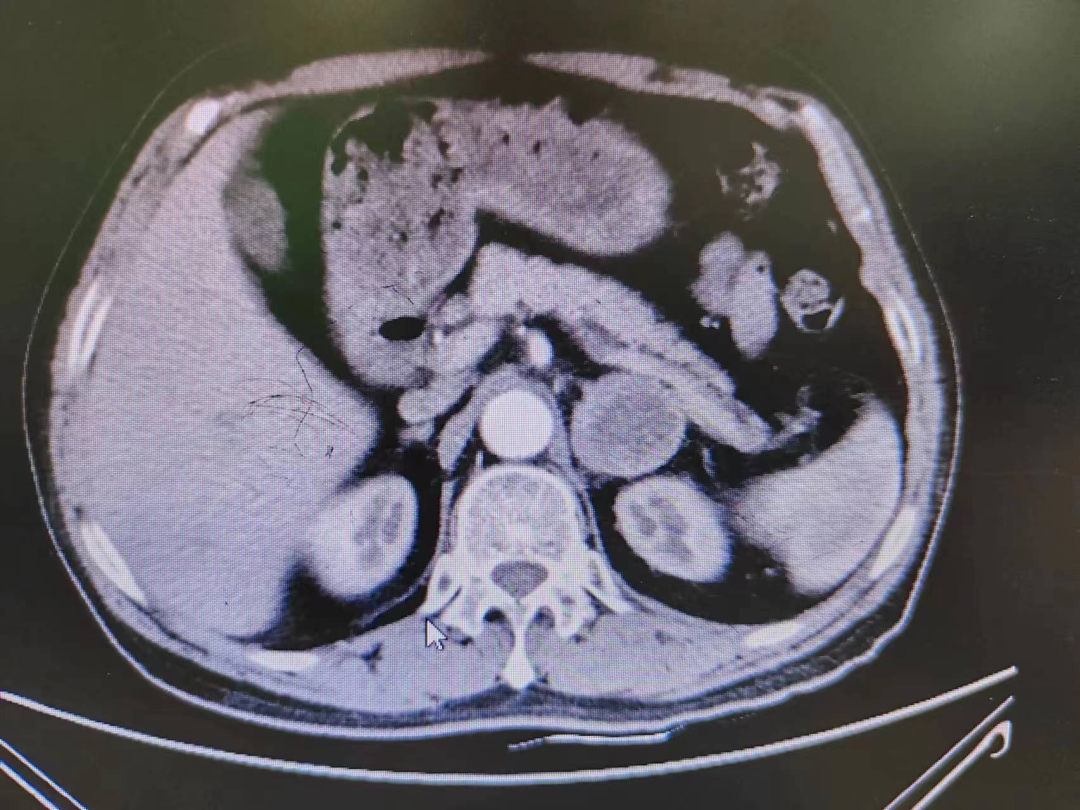

患者熊XX,67歲,因發(fā)現(xiàn)頭暈、頭痛曾多次于外院就診,到新橋醫(yī)院就診完善腎上腺CT考慮嗜鉻細(xì)胞瘤,既往有高血壓病史3年,血壓更高達(dá)230/120mmHg。我院高新區(qū)院區(qū)開診后,患者慕名而來。術(shù)前積極完善血尿兒茶酚胺代謝產(chǎn)物(MNS)均明顯升高,患者于我院高新區(qū)院區(qū)及江南院區(qū)泌尿外科積極控制血壓、心率、血糖,術(shù)前充分?jǐn)U容。

因腫瘤位置位于腎蒂周圍,術(shù)中觸碰腫瘤導(dǎo)致血壓明顯升高,血壓波動(dòng)較大,腫瘤表面血供豐富,不僅需要手術(shù)醫(yī)生豐富的臨床經(jīng)驗(yàn)和高超的技術(shù)水平,也是對(duì)醫(yī)生心理素質(zhì)、勇氣和毅力的嚴(yán)峻考驗(yàn)。

經(jīng)過泌尿外科醫(yī)師全體討論,在進(jìn)行術(shù)前準(zhǔn)備2-3周后,再次請(qǐng)多學(xué)科討論評(píng)估手術(shù)風(fēng)險(xiǎn),并與患者及家屬充分溝通后于6月30日行腹腔鏡下左側(cè)腎上腺嗜鉻細(xì)胞瘤切除術(shù)。手術(shù)在陳勇主任醫(yī)師的指導(dǎo)下,由孫偉副主任醫(yī)師主刀及王傳麟醫(yī)師完成,術(shù)中見腫瘤與腎蒂血管周圍粘連緊密,與腎動(dòng)脈、腎靜脈分界不清,稍有不慎,可能損傷腎蒂血管可能需要行腎切除術(shù),且分離腫瘤過程中血壓波動(dòng)較大。但在孫偉精準(zhǔn)操作及分離下,與麻醉醫(yī)生和手術(shù)護(hù)士團(tuán)隊(duì)密切配合,經(jīng)過2小時(shí)的手術(shù),順利切除嗜鉻細(xì)胞瘤,并保護(hù)好腎臟血管及周圍組織。術(shù)后患者順利出院,術(shù)后血壓及血糖控制良好。